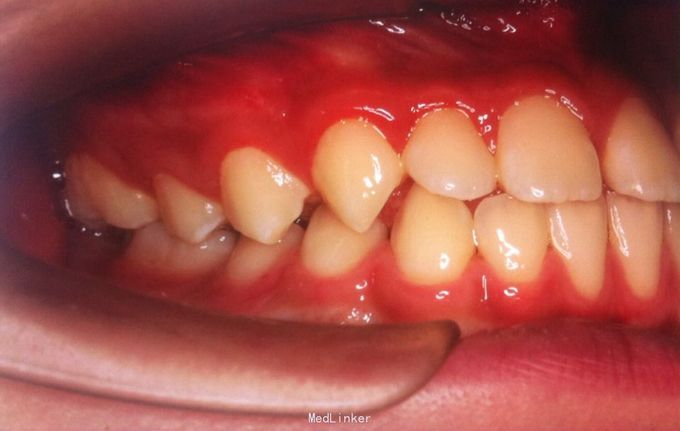

恒牙期 磨牙中性关系 前牙覆合覆盖关系正常 A1B1之间1mm间隙

安氏一类 不拔牙矫治,直丝弓矫治器,排齐整平上下牙列,关闭前牙散在间隙,矫治后磨牙中性关系,前牙正常覆合覆盖,维持现有面型